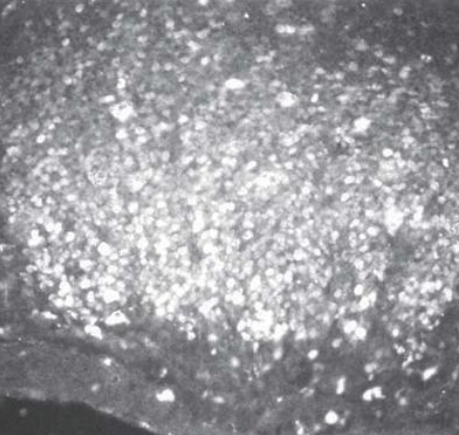

『乳酸菌生成エキス』の摂取による老齢マウス(58週齢)の<パイエル板>にいる免疫細胞の変化

中心部に加齢による退縮がみられる。

中心部が活性化している。